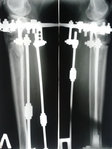

Дата операции 03.12.2014г.

Дата снятия аппаратов 06. 04.2015г.

Срок лечения 4 месяца.